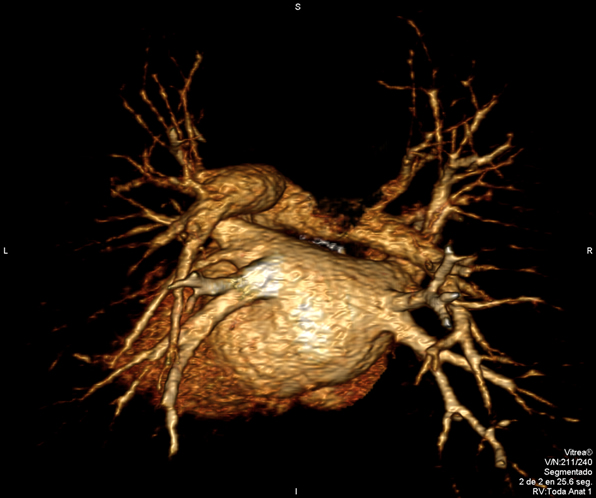

RM Cardíaca

Es una prueba diagnóstica no invasiva que obtiene información morfológica y funcional del corazón y las estructuras adyacentes; de esta manera se pueden diagnosticar diferentes patologías congénitas y adquiridas, o bien realizar controles en pacientes con patología previa ya conocida. En la gran mayoría de casos es necesario el uso de contraste intravenoso (gadolinio) para completar el estudio, un tipo de contraste que raramente produce reacciones adversas. Durante la prueba, el técnico le pedirá varias veces que aguante la respiración durante 10-15 segundos para obtener las imágenes lo más claras posible. No se necesita preparación previa alguna por parte del paciente. La duración de la prueba es de aproximadamente 45-60 minutos. Está contraindicada en pacientes con marcapasos; el paciente debe avisar si es portador de implantes metálicos y/o clips quirúrgicos.